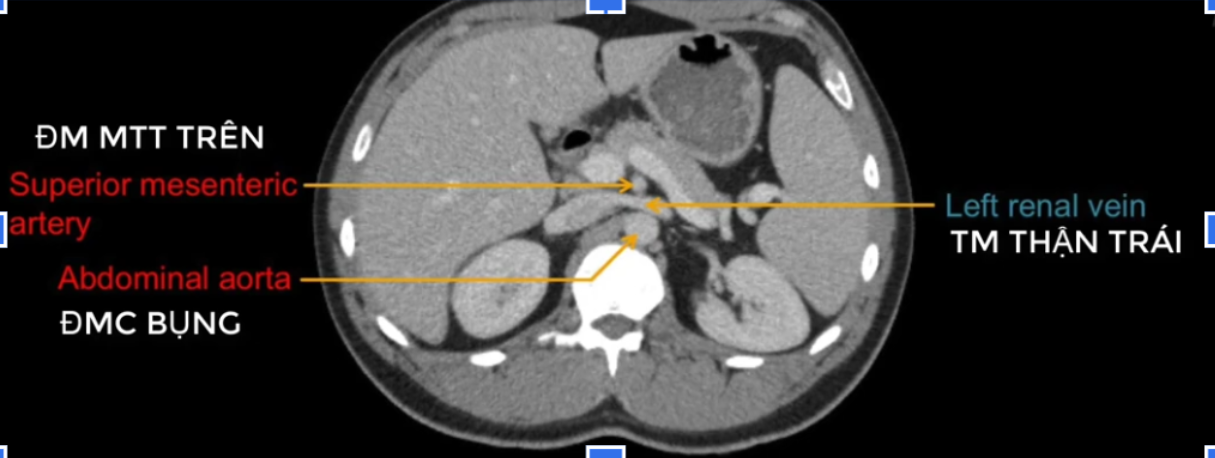

đm thận T?